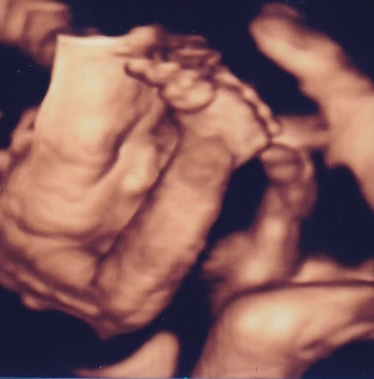

エコーはFujifilmの最新型の機械を導入しました。動く赤ちゃんを立体的にみられる4Dエコーも全例で実施します。赤ちゃんの位置や向きによっては上手くお顔が見えないことや、赤ちゃんによってはなぜかいつも背中しかみせてくれない子もいます。その点はご了承ください。

当院での4Dエコー画像例(患者様には掲載について了承をいただいております。)

27週 女の子